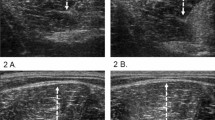

Typical T2-weightened MR images of the right thigh before and following exercise are presented in Fig. 3. The CSA of the ST was increased on the third day (Fig. 4, lower left). The brightness of hamstring muscles increased immediately following exercise. On the third day following exercise, the ST showed a conspicuous increase in brightness (Fig. 5, lower left).

Representative T2-weightened magnetic resonance images of the middle region (50% of thigh length) from one subject before, immediately after, and on the first, second, third, and seventh days following eccentric exercise (BFs biceps femoris short head muscle, BFl biceps femoris long head muscle, ST semitendinosus muscle, SM semimembranosus muscle)